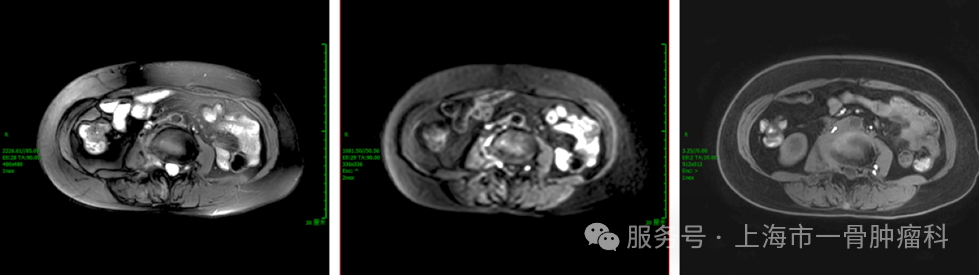

图6: 2025年3月,介入治疗前

图7: 2025年5月,介入治疗三次后

经过4个周期的DSA灌注治疗,联合术前骨水泥稳定术,患者的病灶获得良好控制,MRI复查显示椎体及椎旁肿瘤均明显缩小,神经结构压力减轻。临床上,患者疼痛评分下降70%以上,日常功能恢复,生活质量显著改善。